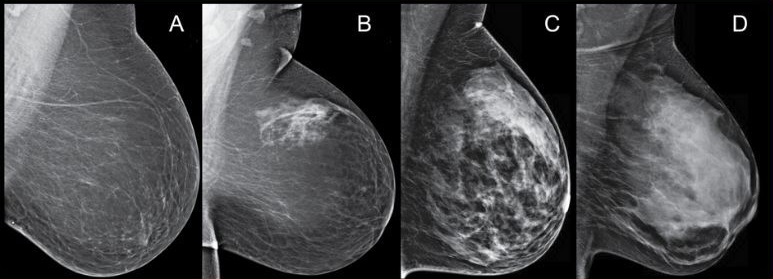

- после сорока лет — обязательна маммография (рентгеновский снимок груди в двух проекциях, выполняется в первой фазе цикла);

- цифровой томосинтез — послойные снимки молочной железы для реконструкции объёмного изображения в специальной программе (даёт высокую визуализацию органа, помогает поставить диагноз при неоднозначных результатах маммографии).

Полученные результаты оценивают по критериям BI-RADS. Это позволяет оценить риск онкологического перерождения молочной железы в балльной системе.